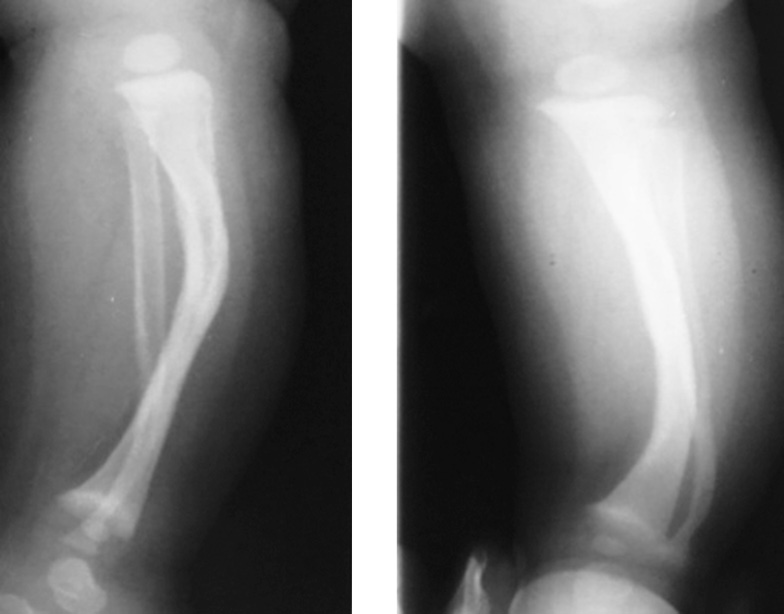

The anamnesis revealed that the child was sick from birth. Limb deformity, as a latent form of a false joint, was detected at the age of 5 months (Fig. 1). At the age of 1 year, a pathological fracture occurred (Fig. 2). The patient underwent repeated operations at the primary care facility. At the age of 1.5 years, autoplasty of the false joint area was performed with a graft from the iliac crest with a hardware fixation. One month after the intervention, the migration of this structure was noted, for which repeated plastic surgery was performed using a graft from the iliac crest with a pin, also with repeated migration of the hardware. Owing to the lack of consolidation of the tibial fragments, the fragments were fixed with an intramedullary rod using autoplasty of the defect with a graft from the tibia of the contralateral limb. Subsequently, the rod was removed, union was not achieved, and significant bone lysis was detected.

Fig. 1. X-ray imaging of the right lower leg bones in two views with a latent form of pseudarthrosis

Fig. 2. X-ray imaging of the right lower leg bone with a pathological fracture